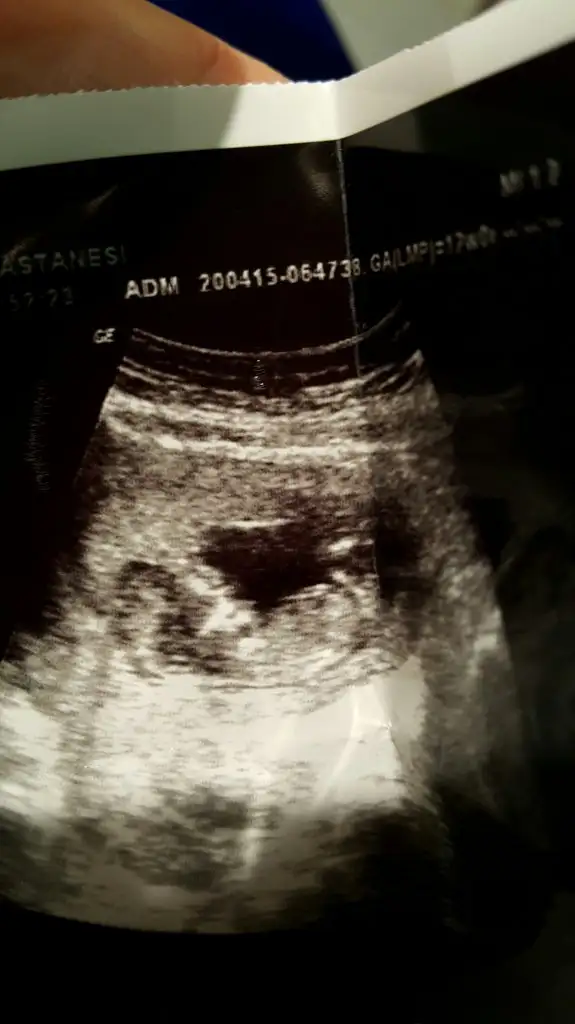

Hastaneden geldim son halimiz 18 haftalikmis bi bakın kizlarrrrr belki gorursunuz

Kızlar ben yeni üyeyim.bir kızım var,ikinciye hamileyim.12+1günlük ultrason görüntüsünü yüklüyorum.bana da yorum yapar mısıniz?dr bacakları kapalı,göremedim.bu halde tahminde bulunursam kız gibi dedi.bu haftalarda yanılma payı çok olur diye yorum yapmak istemedi,ben ısrar edince kız gibi dedi.bacak arası kapalı olunca böyle düşündügünü söyledi.

benim bebişim içinde tahmin de bulunur musunuz?yukarıda ultrason görüntüsünü yükledim.4boyutlu görüntüsünü de yüklüyorum.15.hafta da net bişey söyleriz dedi dr.

Orkidecim,bir yorum da benim bebişime yapabilir misin?burda ki görüntülere bakınca ben kıza benzettim.2hafta sonra dr gidecem.kızlar sizlerden yorum bekliyorum